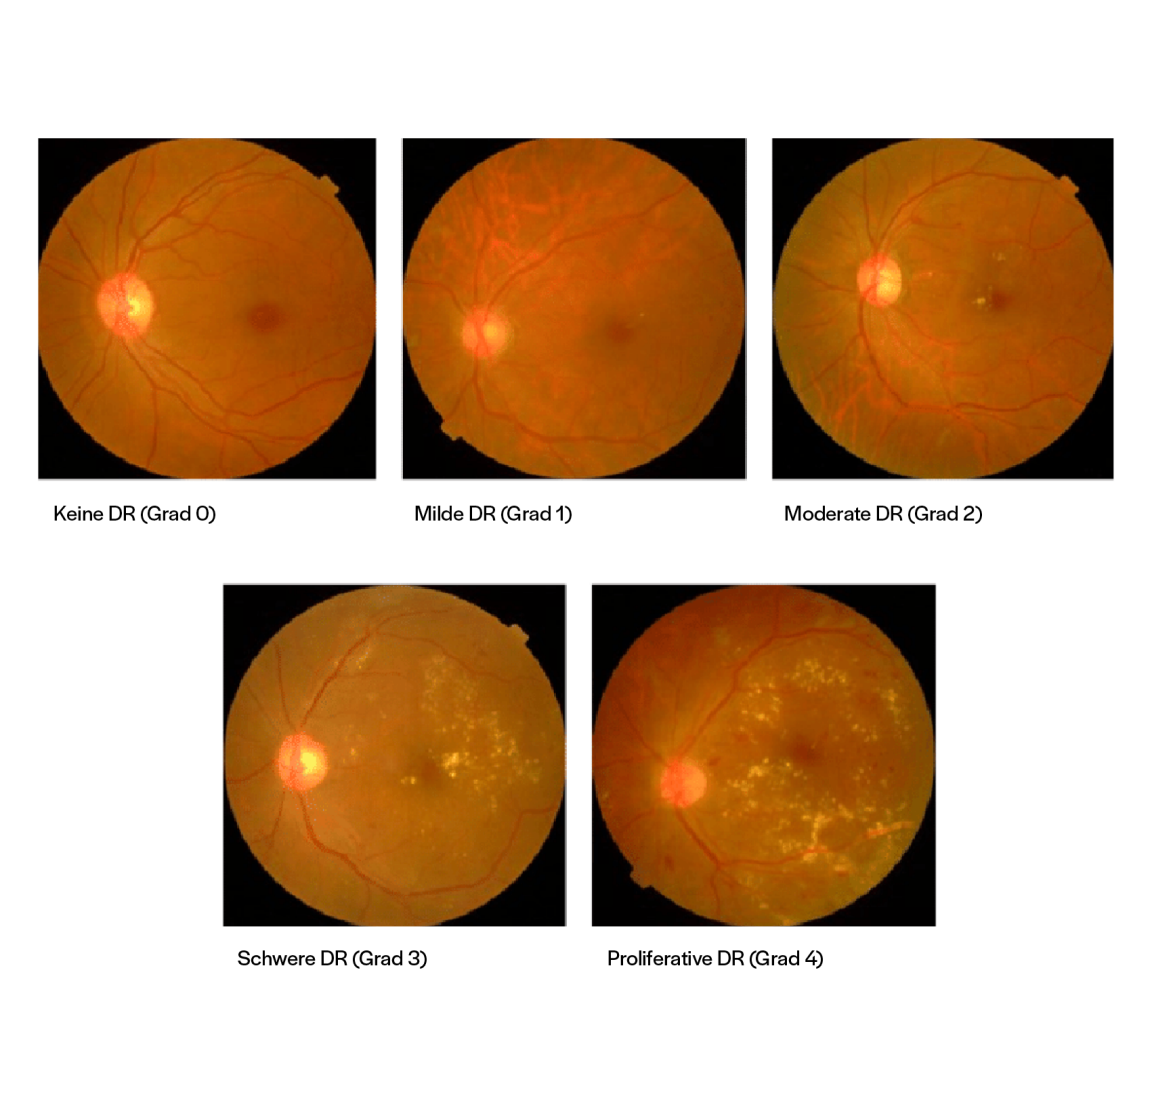

Aufnahmen von Augenwänden mit Graden der diabetischen Retinopathie

Abbildung 1: Repräsentative Aufnahmen, die die Bandbreite von einer gesunden Netzhaut (Grad 0) über die nicht-proliferativen Stadien (Grad 1–3) bis zur proliferativen diabetischen Retinopathie (Grad 4) veranschaulichen (Quelle: APTOS-Datensatz).